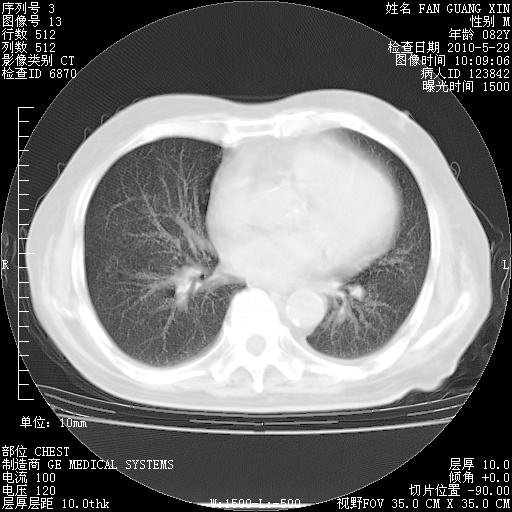

再治疗10天后的肺部CT

再治疗10天后的肺部CT 纵膈窗

阅读此次胸部CT,肺间质渗出性改变较入院时有吸收。目前从体温、白细胞、中性分叶明显增高,肯定存在细菌感染(发生医院感染哦,若无消化道及泌尿系统等感染的依据,肺部感染可能大)。若你院头孢哌酮舒巴坦钠耐药率较高,同意你的方案,若48小时体温仍高,可考虑使用碳青霉稀类抗菌药物,同时可予超声雾化、注意滴数时加大液体量。白蛋白33.30g/L较低哦,需加强营养等支持治疗。